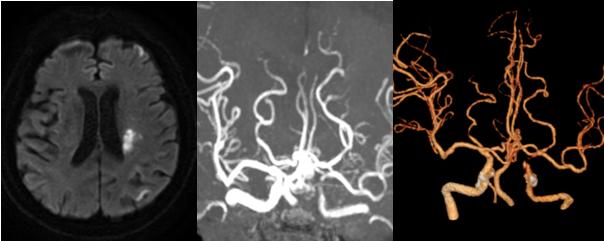

神经内科董万利主任带领团队对胡大爷的病情进行了分析评估。患者头颅磁共振发现左侧大脑中动脉供血区多发脑梗死,CTA+CTP检查提示:左侧颈内动脉颅内段混合斑块,管腔中-重度狭窄,最狭窄处接近闭塞;左侧大脑中动脉供血区缺血性灌注异常。诊断为:“脑梗死,左侧颈内动脉颅内段次全闭塞”。

神经内科郝永岗副主任医师与神经血管介入团队充分讨论患者病情,完善术前相关检查及药物准备,排除禁忌症,决定为患者实施经皮左颈内动脉颅内段球囊扩张成形术。9月8日,我院神经血管介入团队在MRI-DSA杂交手术室于局部麻醉下为患者实施手术,历时70分钟,成功扩张成形病变血管,使脑血流明显改善,挽救了处于缺血状态的神经细胞,避免了梗死核心进一步扩大。术后经过神经内科及康复医学科联合积极治疗,胡大爷右侧肢体肌力明显增强。